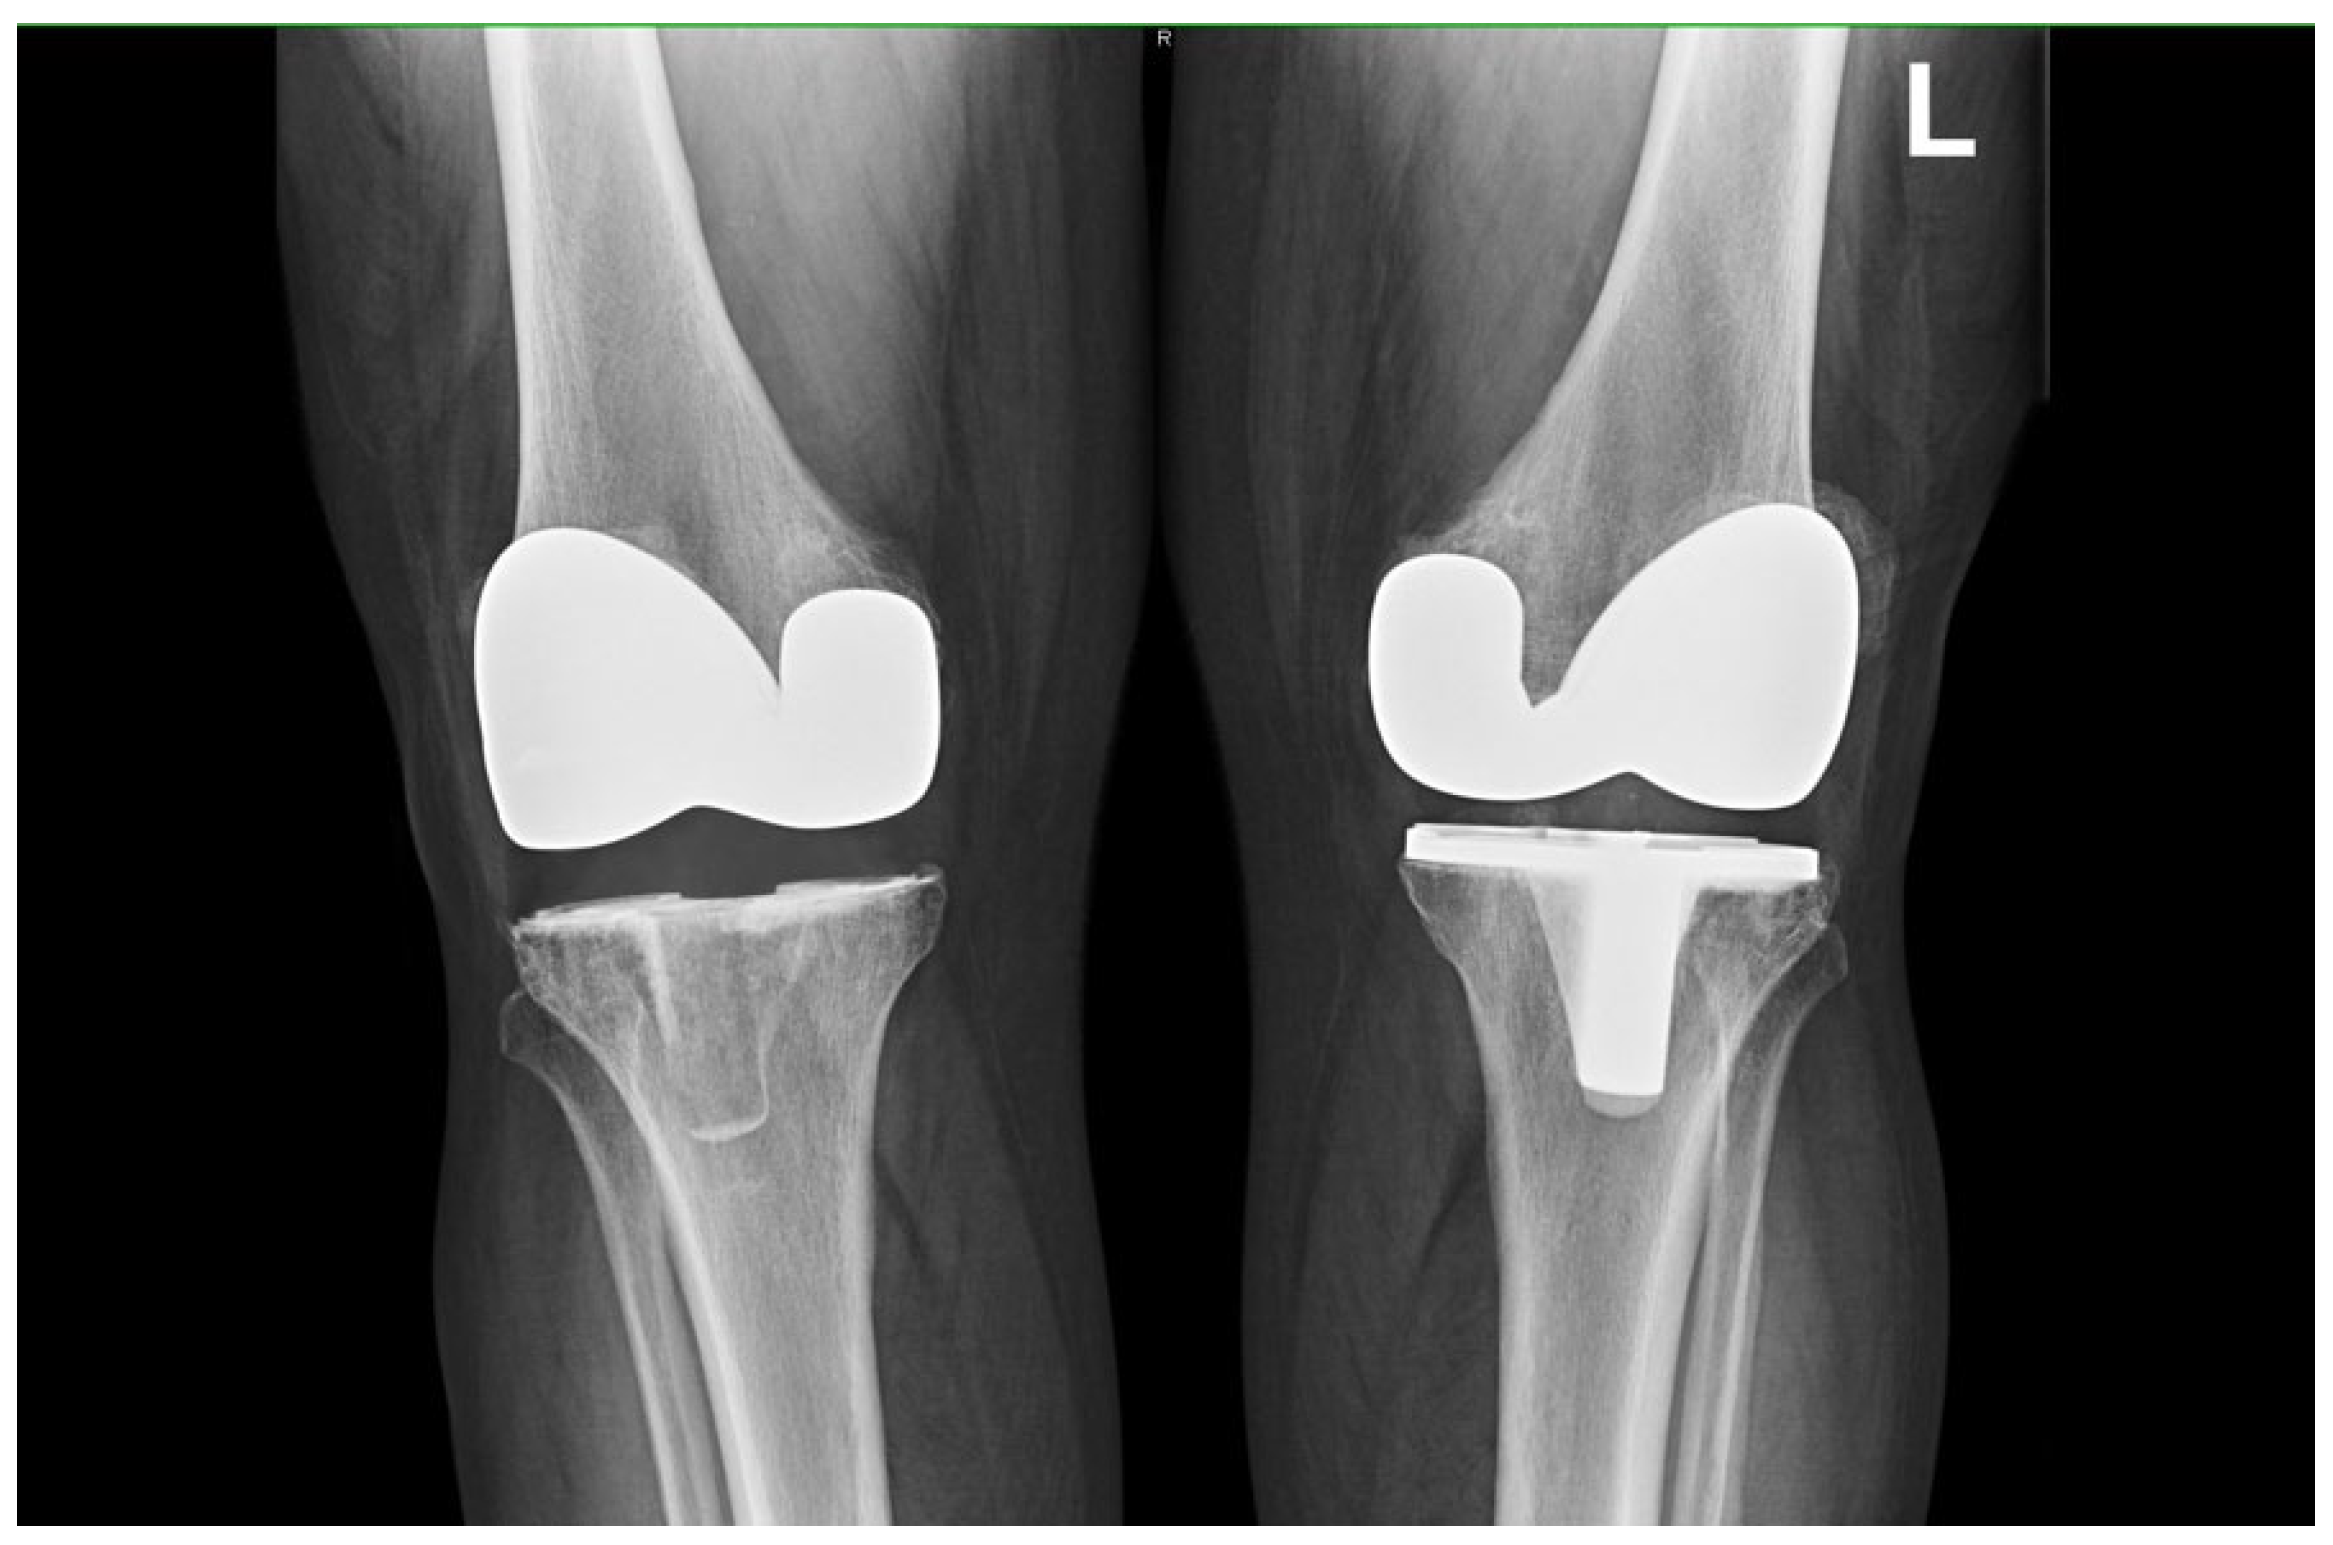

Implant Preference and Clinical Outcomes of Patients with Staged Bilateral Total Knee Arthroplasty: All-Polyethylene and Contralateral Metal-Backed Tibial Components

2.3. Implant Types